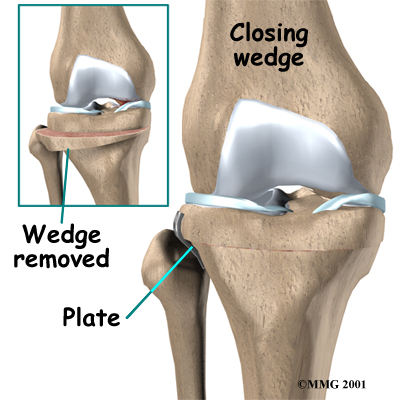

There are two methods to realign the knee joint. One involves taking out a wedge of bone; the other involves adding a wedge of bone. Any operation for cutting through a bone is called an osteotomy. In a closing wedge osteotomy, the surgeon cuts though the tibia on the lateral side, removes a wedge of bone, and pins the open edges together. In an opening wedge osteotomy, the surgeon cuts though the tibia on the medial side and opens a wedge, adding a bit of bone graft to hold the wedge open.

Closing Wedge Osteotomy

In the , an incision is made in the lateral side of the knee to allow the surgeon to see the upper end of the tibia. Care is taken to protect the nerves and blood vessels that travel across the knee joint.

Once the tibia bone is exposed, two cuts are made through the upper tibia in the shape of a wedge. The surgeon uses either X-rays or a fluoroscope, a special kind of X-ray machine that casts images on a fluorescent screen, to make sure the wedge is the right size and is placed correctly.

The surgeon takes out the wedge, and the two sides of the tibia are brought closer together and held in position with a metal plate or pins. This and helps straighten the alignment of the knee. After fixing the two edges of bone with a plate or pins, the surgeon stitches the skin together, and the leg is placed in a padded splint to protect the knee joint.